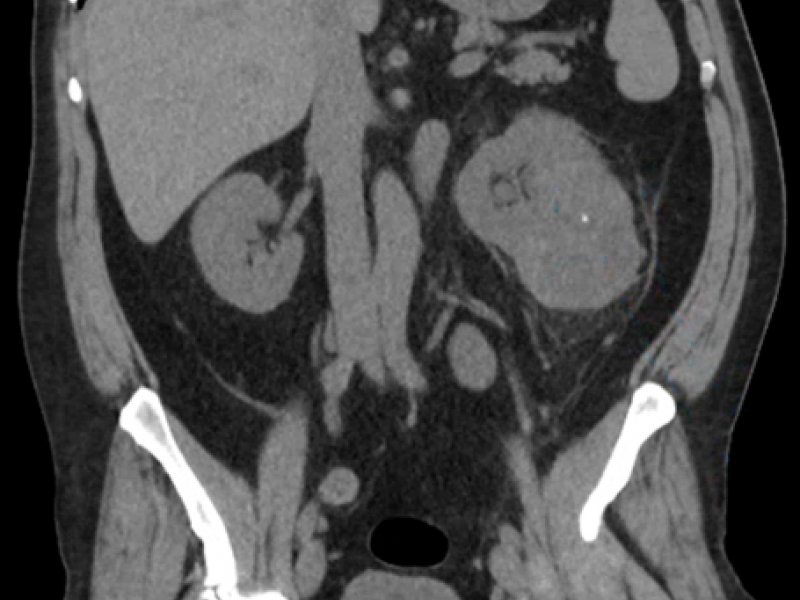

What's the Diagnosis? By Dr. Loran Hatch

40 yo M presents to ED complaining of L flank pain w/